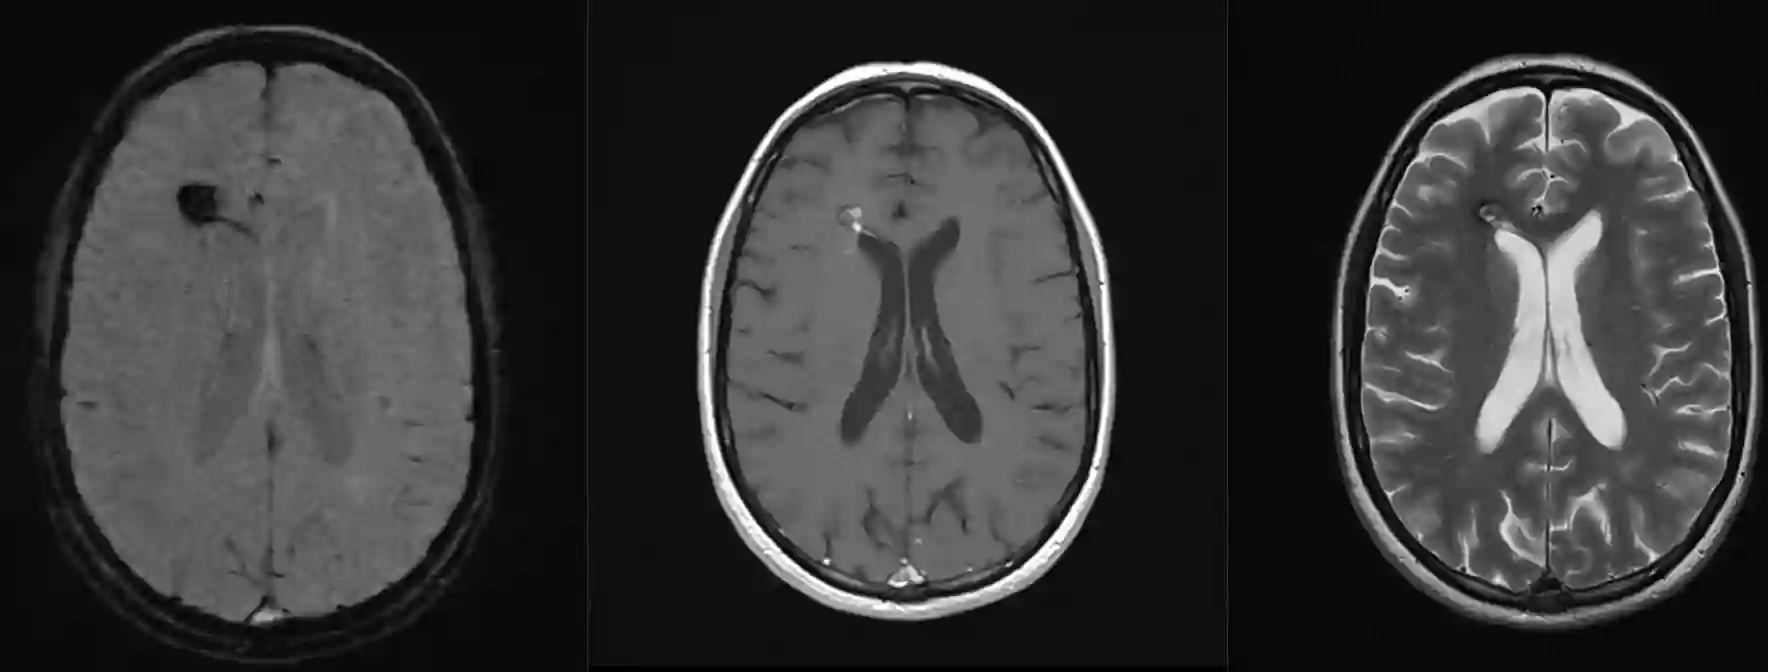

Der Goldstandard in der Diagnostik von Kavernomen ist die MRT Bildgebung.

Die Diagnose von Kavernomen erfolgt üblicherweise mit einer MRT Bildgewebung wobei insbesondere die T2 und SWI Sequenz hilfreich sind. Kavernome zeigen im MRI typischweise eine "Popkornartige" bzw. "Maulbeerenartige" Struktur. Die Einteilung erfolgt häufig nach der Zabramski Klassifikation. Eine digitale Subtraktionsangiographie führt zu keiner Darstellung von Kavernomen, kann jedoch in der Diagnostik zum Ausschluss anderer Gefäßpathologen in unklaren Fällen eine Rolle spielen[^1].